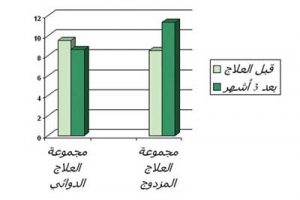

يوضح الرسم تأثير العلاج المزدوج والعلاج الدوائي منفردا على النسبة المئوية للخلايا القاتلة الطبيعية في كل من المجموعتين

رابعا: نتائج الفحص المعملي للعدد الخلايا الطبيعية القاتلة :

• قبل البدء بالعلاج:

أظهرت الدراسة وجود انخفاض ذا دلالة إحصائية في النسبة المئوية للخلايا القاتلة الطبيعية لدى مجموعة مجموعة مرضى مقارنة بنظيره في الروماتويد الأصحاء. بينما ثبت إحصائيا عدم وجود فارق ذا دلالة إحصائية بين مجموعتي المرضى من حيث النسبة المئوية للخلايا القاتلة الطبيعية

• بعد ثلاثة أشهر من العلاج:

ارتفعت مؤشرات النسبة المئوية للخلايا القاتلة الطبيعية NK cells في المجموعة التي تلقت العلاج بالحجامة إلى جانب العلاج الدوائي , بينما ثبت انخفاض النسبة المئوية للخلايا القاتلة الطبيعية في مجموعة العلاج الدوائي وقد يبرر ذلك تأثير الأدوية المثبطة للمناعة. وارتفاع النسبة المئوية للخلايا القاتلة الطبيعية بعد تطبيق جلسات الحجامة يعني استنفار وتحفيز القدرة المناعية لتلك الخلايا المحبطة عادة في مرضى الروماتويد بفعل الأدوية المثبطة للمناعة أو بسبب إضطراب نشاط الجهاز المناعي ككل في مرضى الروماتويد . وانخفاض معدل تلك الخلايا أو انخفاض نشاطها يزيد من خطر التعرض للتحولات السرطانية والاصابة بالعدوى المتكررة . حيث تقوم تلك الخلايا بحراسة الجسم من أي هجوم فيروسي أو بكتيري أو طفيلي, كما تلعب دورا حيويا في مهاجمة الخلايا المتحولة (السرطانية).